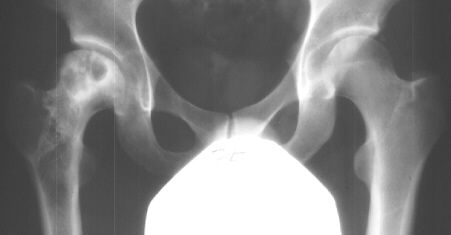

At 28 years of age, he had been having increasing pain in his right hip. He had a limp when he was tired. Positive Trendelenburg's sign was observed on the right. Internal rotation was limited to 25 degrees. All other motions were normal. X-ray showed cystic change. At the 29 years of age, he underwent bone graft of the right femoral head for degenerative cyst. At 35 years of age, only internal rotation was limited to 20 degrees. He still had pain in his hip that relates primarily to weather or to excessive walking. Only internal rotation was limited to 20 degrees. He had hip pain at the extremes of flexion and internal rotation. X-ray showed the progression of the cystic change. CT which was performed because of the question of loose bodies in the hip did not seem likely that the densities were actually in the hip joint. The antero-medial location of the cysts facing the anterior margin of the acetabulum was well depicted in CT.

28 yrs, 29 yrs, 30 yrs, 35 yrs .